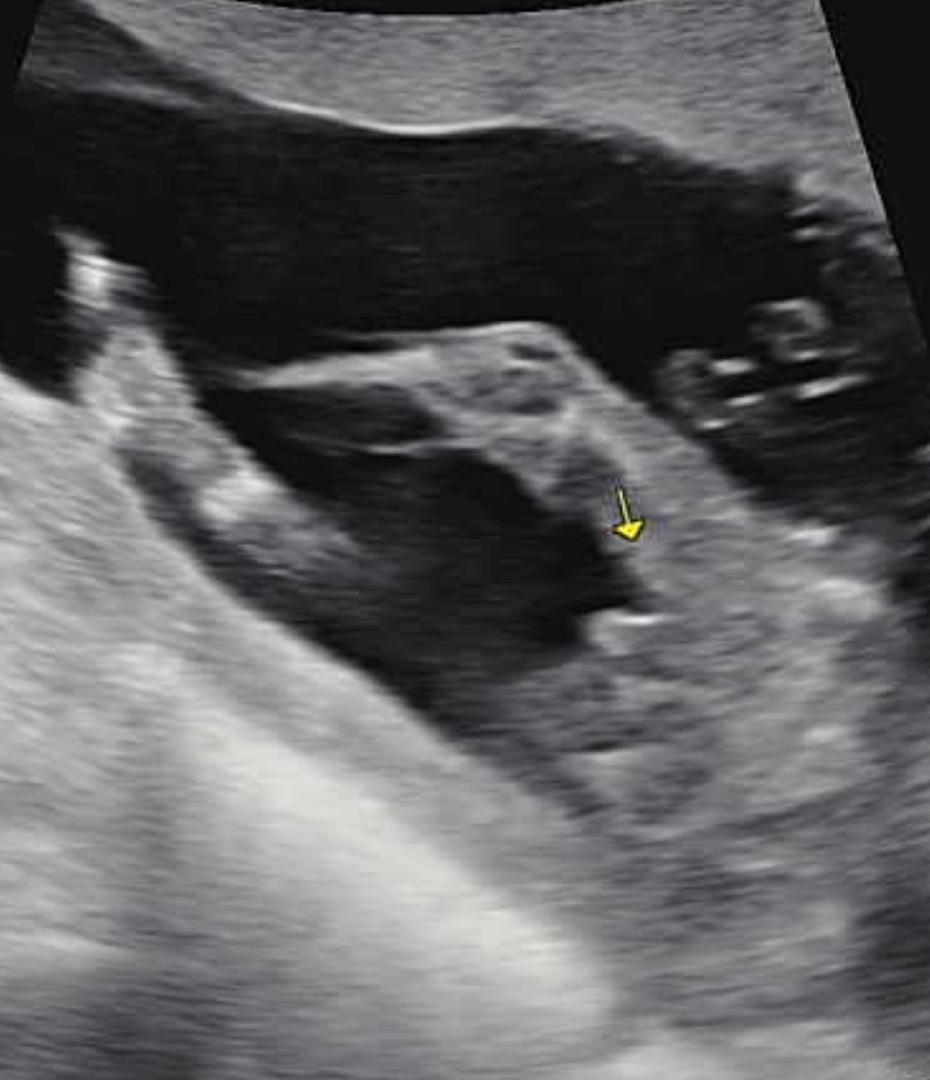

혹시 이게 고추...?인가요?

16주 초음파 사진인데 선생님도 아들인것같은데 잘모르겠다고 하셨오요 이정도면 고추 맞는거죠? 첫 아이라 너무 궁금하네요😂

16주에 저정도 사이즈면 반전 있을수도 있을것같아요~~ 좀만 더 지나고 확인해보세용

저는 좀 더 미사일 처럼 생겨서 아들 확정 받았는데 저정도여도 아들 맞는거 같아요! 들어갈거 같지 않아보여용 아들 축하드려요👋🏻